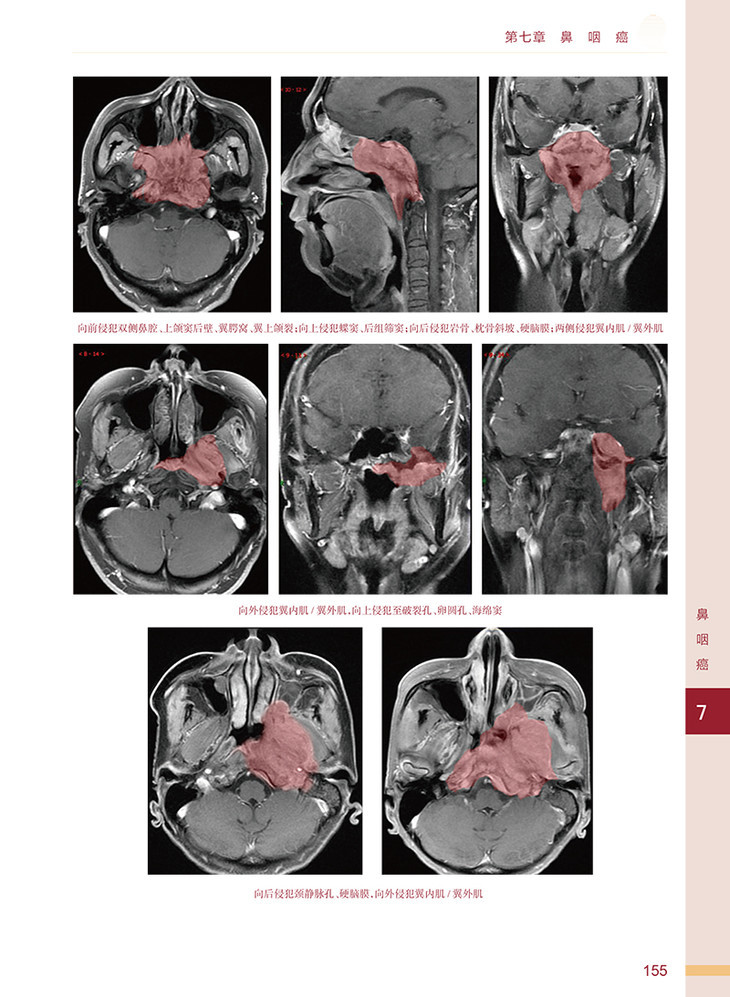

1. 新补充的病例多同时采用 CT 与 MRI 的融合图像技术,对于辨认肿瘤和精准靶区勾画有很大帮助。

2. 补充了相关肿瘤侵犯范围的CT/MRI 图像,以及治疗病例的失败模式,对于正确理解相关肿瘤的生物学行为和调强放疗靶区的勾画有参考和借鉴意义。